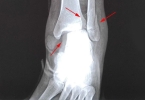

3、创伤:如足部挤压、碰撞、硬物撞击、抓挠等损伤,导致足部肌肉、肌腱等组织损伤,可能出现疼痛、血肿、出血等症状。患者在碰伤后24小时内发现充血,或充血缓慢增加,可使用冰块或冷毛巾冷敷。

除上述原因外,它也可能是由骨折引起的。如果脚站一段时间疼痛症状,应注意休息,减少活动和负荷,避免长时间站立和蹲下,以免加重疼痛症状。